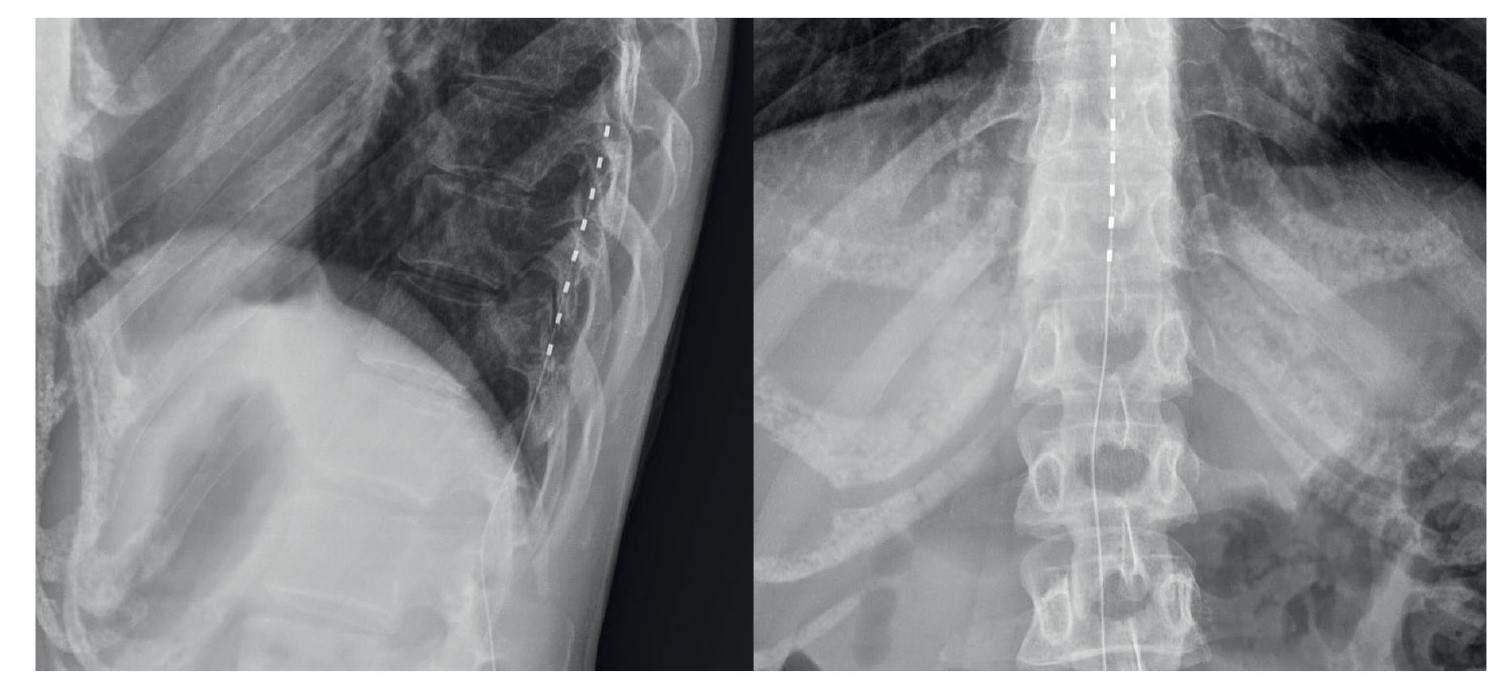

Patient S., a 32-year-old female, underwent surgical removal of a subcutaneous lipoma located on the dorsolateral surface of the left foot posterior to the lateral malleolus. In the early postoperative period, she developed a severe burning pain syndrome radiating along the lateral foot surface, accompanied by paresthesias and hypesthesia of the toes. Pain intensity reached 8 points on the visual analog scale (VAS). Neurological examination and instrumental diagnostics confirmed iatrogenic injury to the sural nerve (n. suralis) in the surgical access area. Sequential attempts at surgical management (marginal neurectomy) and conservative therapy (gabapentin 900 mg/day, duloxetine 60 mg/day, venlafaxine 150 mg/day) proved ineffective, showing only short-term analgesic effects with pain recurrence before subsequent dosing. In 2022, the patient underwent implantation of a chronic spinal cord stimulation (SCS) system at Th10-Th12 levels (Fig. 1). Stimulation-induced paresthesias covered 80% of the pain area and reduced pain intensity by 30%.

Fig. 1. Radiographic image of the implanted electrode in the posterior epidural space at the T10–T12 vertebral levels.